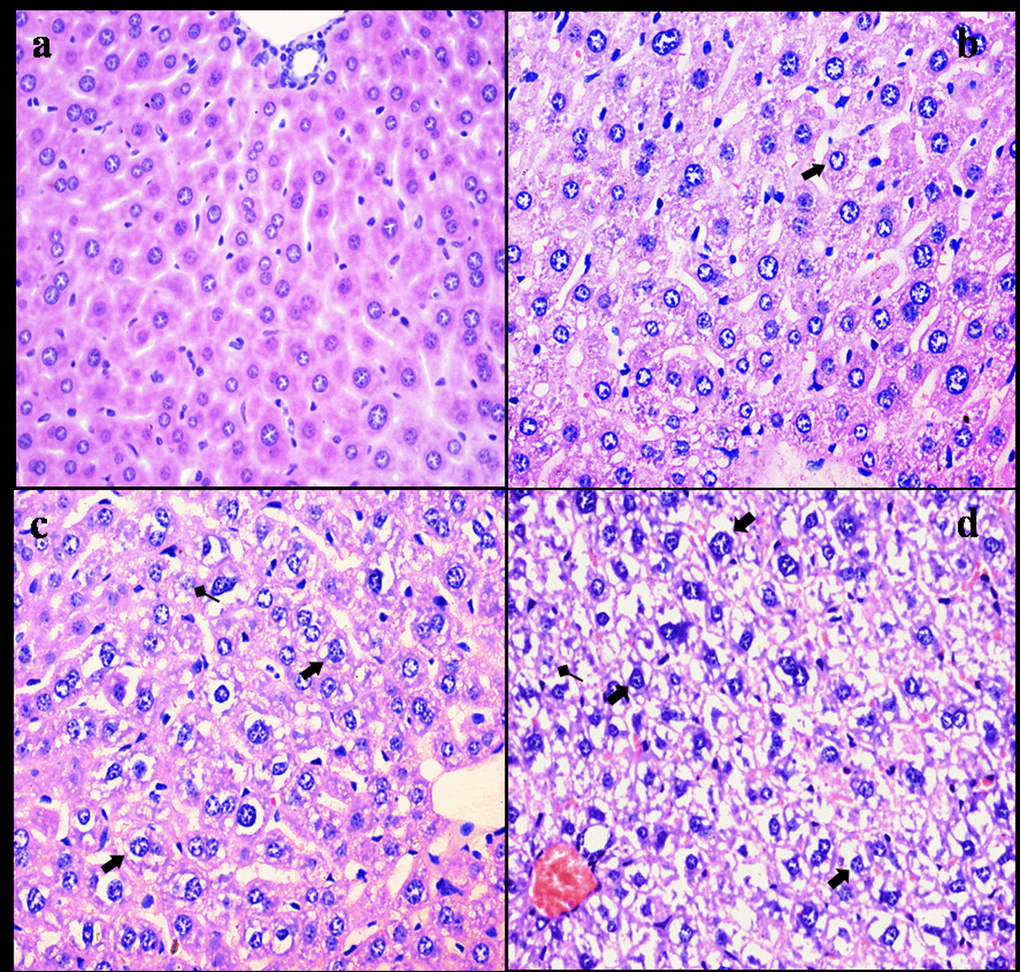

NaF resulted in histopathological lesions in a dose- and time-dependent manner. Lesions included hepatocellular granular degeneration, vacuolar degeneration and necrosis. In the granular and vacuolar degenerated hepatocytes, tiny particles and small or large vacuoles were appeared in the cytoplasm (Figure1). Karyorrhexis, karyolysis and hypochromatosis were appeared in the necrotic hepatocytes (Figure2). The above lesions were not observed in the control group.

Figure 2. Histopathological changes in the liver at 42 days of the experiment. (a) The control group (H&E × 400). (b) The 12 mg/kg group. Hepatocytes show granular and vacuolar degeneration (⇑, H&E × 400). (c) The 24 mg/kg group. Hepatocytes show obvious granular and vacuolar degeneration (⇑). Also, necrotic hepatocytes are observed (↑, H&E × 400). (d) The 48 mg/kg group. Hepatocytes show marked vacuolar degeneration (⇑). Necrotic hepatocytes are observed (↑). And hepatic cords are disorganized or disappeared (H&E × 400).